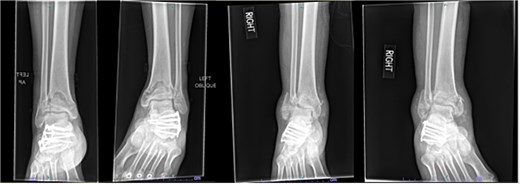

Despite the patient’s noncompliance, he went on to heal uneventfully for the next 2 years until the patient fell from a height of 15 feet, resulting in a left bicondylar tibial plateau fracture and fracture of the left tibial shaft. These injuries required ORIF of his left tibia. Despite the new injury, the hardware from the pilon fractures was in proper alignment (Fig. 4).

Two-year follow-up AP and lateral radiographs of both ankles in patient 2 showing maintained alignment and hardware position.